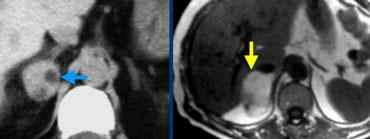

Đây là hình ảnh của bệnh nhân nữ 65 tuổi, phát hiện tình cờ khối tuyến thượng thận phải trên siêu âm ổ bụng được thực hiện vì sỏi thận.

Sự hiện diện của mỡ vi thể được chứng minh bởi sự giảm tín hiệu trên ảnh đảo pha.

Bệnh nhân được theo dõi trong 2 năm do tổn thương hơi không đồng nhất và có kích thước 5,2 cm.

Tổn thương không thay đổi kích thước và không có hoạt động nội tiết.

Tổn thương được chẩn đoán là u tuyến nghèo lipid.